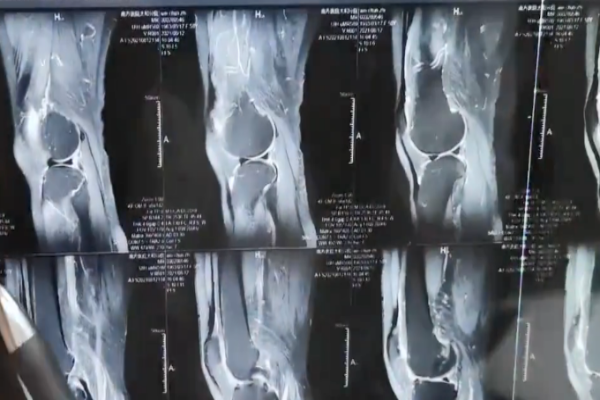

經過醫生一系列檢查,以及核磁共振的結果顯示,吳老太的髕骨,以及膝蓋軟骨,幾乎全部出現了花瓣狀的磨損,並且在半圓板後的關節骨骼處,還出現了細微的骨骼現象,且傷勢遲遲沒有發現,吳老太的關節內也全是積液。